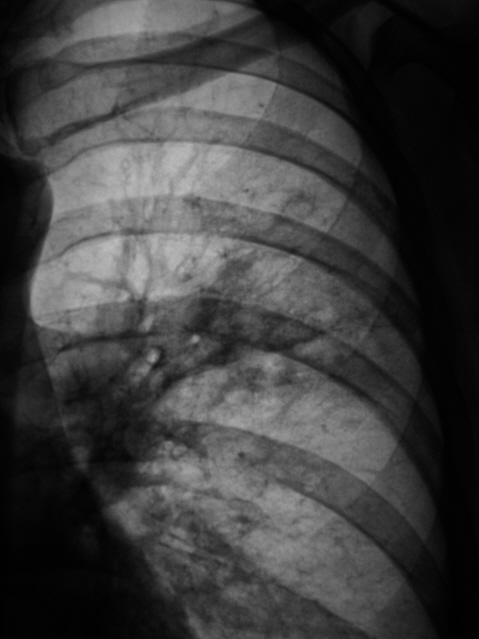

После расшифровке флюорограмм пациент "взят на контроль" - 1, 2.

Произведено стандартное дообследование пациента - рентгенография (3, 4, 5) и томография (6, 7, 8, 9, 10, 11). Была заподозрена онкология, однако изменения на томограмме - срез 7 см. (9, 10, 11), склонили нас в пользу изменений воспалительного генеза. Было решено провести адекватную противовоспалительную терапию. После проведения противовоспалительной терапии был произведен рентген-контроль ( 12, 13, 14, 15).

А почему уважаемый Валентин Львович была заподозрена онкология? На представленных снимочках хорошо видно перибронхиальную и перивоскулярную инфильтрацию легочной ткани, сегментарная пневмония.